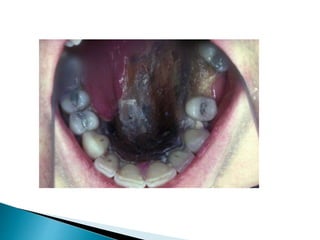

 Symptoms directly related to the invasive disease

take months to years to develop.

 The disease is usually persistent and recurrent.

Maxillofacial soft-tissue swelling develops

with destruction of the bony sinus walls. Invasion

of the maxillary floor leads to palatal erosions.